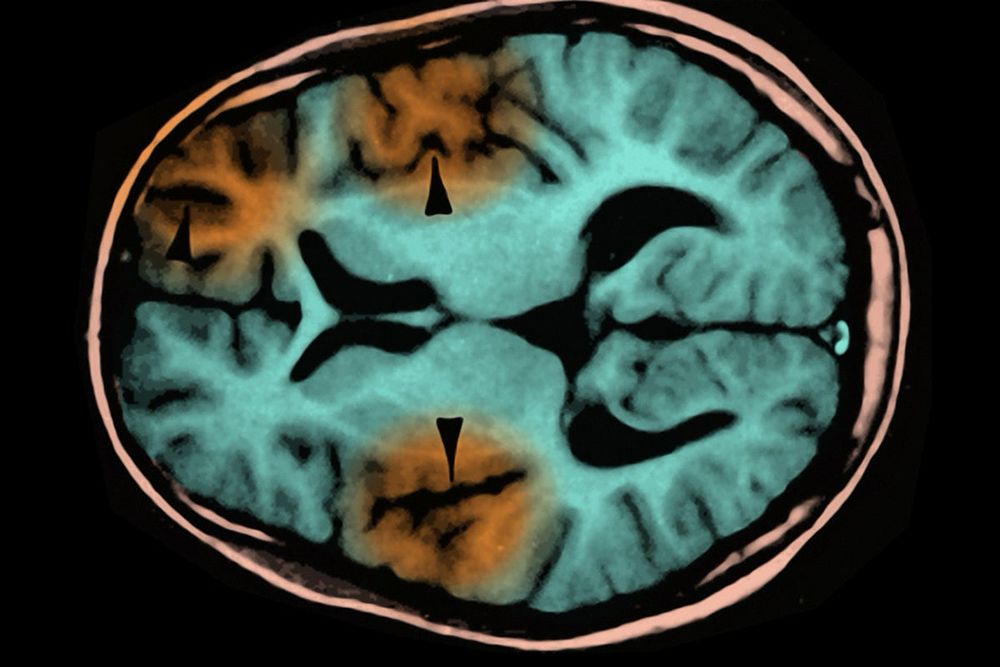

Vaccine-preventable diseases, however, DO cause child deaths. Today, in high-income countries with excellent health care. Measles doesn’t have a cure or specific treatment. When complications arise, only supportive care is available; most kids recover, some don’t. Some do and die later.

Measles in the Brain Can Kill Years after Infection, Child’s Death Shows

A child in Los Angeles County has died from a rare but always fatal brain disorder that develops years after a measles infection. Experts underscore the need for vaccination to protect the most vulner...